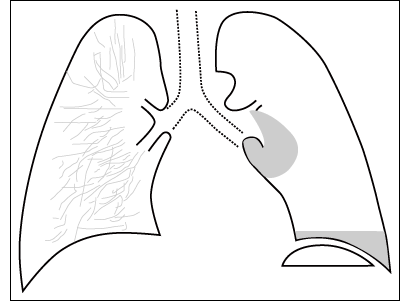

| ESQUEMA 48

Comentario placa 48 Además de una amplia cámara de neumotórax al lado izquierdo se observa en la base de este hemitórax una sombra homogénea de límite superior horizontal. Se trata de un neumotórax con acumulación de líquido pleural o hidroneumotórax. Por en la gran cámara del neumotórax una interfase aire-líquido, se produce un límite horizontal muy neto (imagen hidro-aérea). |